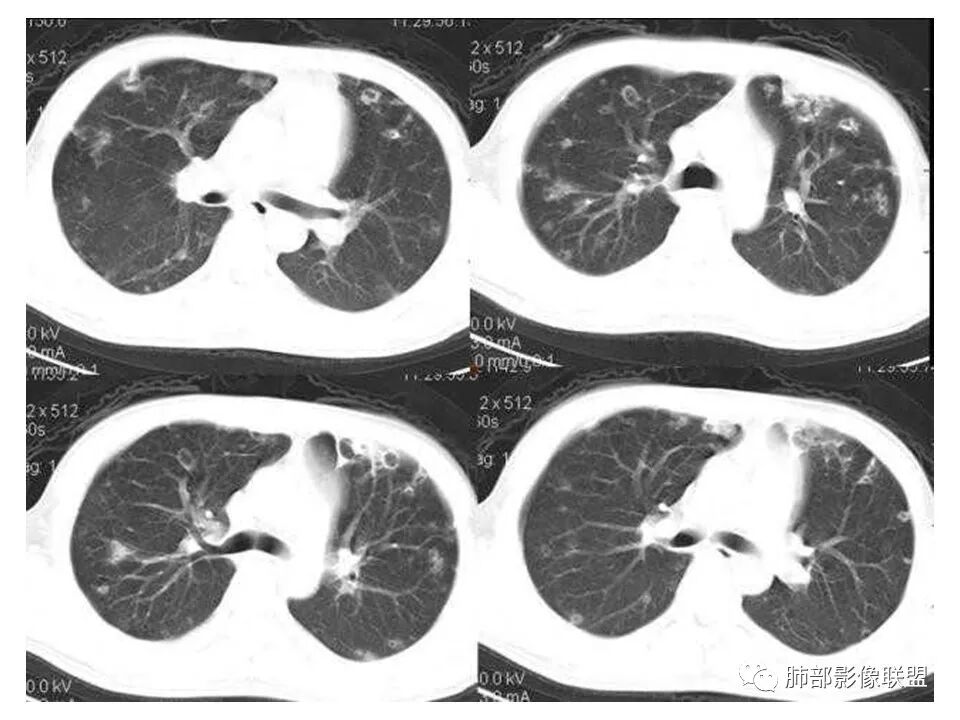

南边:青年男性,急性起病,多发结节或囊腔——胸膜下分布结节,与支气管关系不密切,支气管壁不增厚,首选血道来源,不是气道来源

南边:

血道来源的:

1、感染性:金葡菌?克雷白杆菌?曲霉菌?

2、血管炎性:血管炎?

3、肿瘤:血管肉瘤?转移瘤?

结果

(血源性)金葡菌肺炎(血培养金黄色葡萄菌)

金黄色葡萄球菌:革兰阳性菌,涂片表现为成对的短链状四联球菌或簇状。金葡菌肺炎:是由金黄色葡萄球菌引起的急性化脓性肺部感染,常发生于免疫功能受损的病人。主要分为原发性(吸入性)金葡菌肺炎和继发性(血源性)金葡菌肺炎。血源性金葡菌肺炎:常继发于金葡菌败血症及脓毒血症,由细菌栓子经血液循环至肺而引起。多表现为肺外周和基底部分布为主的多发点片状影或类圆形结节影。菌栓引起多发性肺小动脉栓塞,导致双肺多发性化脓性炎症,进而组织坏死形成多发性肺脓肿,并可累及胸膜产生脓胸或脓气胸。诊断要点:    1.金黄色葡萄球菌引起3%的社区获得性肺炎及15%的  医院获得性肺炎    2.金黄色葡萄球菌肺炎的主要危险因素是静脉输液和ICU患者。    3.常见的影像学表现:    1)单侧(60%)或双侧(40%)斑片状实变影(支气管肺炎)    2)空洞性结节(直径4~10mm)

3)CT可见小叶中心结节、树芽征及楔形变(脓毒性栓塞)

4)肺气囊形成

5 ) 脓肿形成

6 ) 胸腔积液

少见的影像学特征:弥漫性肺实变(表示支气管肺炎融合)

1.金黄色葡萄球菌肺炎是典型的肺部化脓性感染之一。临床中毒症状明显,常寒颤高热起病,脓性痰、血丝痰等。

3.病情变化快,影像进展迅速,尤其是血播患者。易形成脓肿。

4.影像典型血行播散的特点,脓毒栓子,结节影,片影等。

5.短期内(如一两天内)迅速出现的有张力的菲薄气囊影,或多发成串成簇分布的,尤具特征性!这也明显有别于肺炎克雷伯杆菌肺炎及曲霉病。